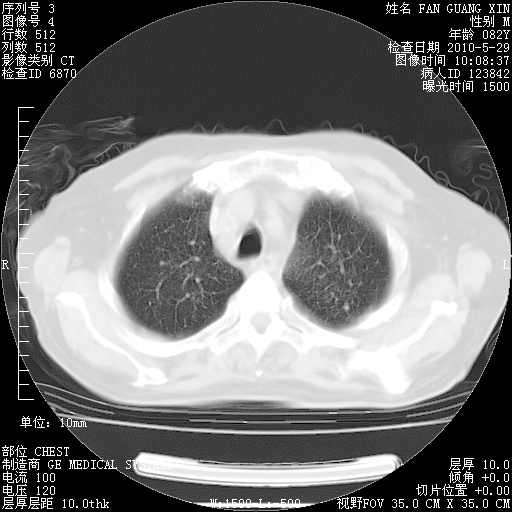

再治疗10天后的肺部CT

肺部体征:呼吸25次/分,心率100次/分,呼吸音增粗。无干湿罗音。

血常规:15.36×10 [sup]9[/sup]/L  N0.92  L0.036  M0.045 ESR 27mm/h。

血生化:白蛋白33.30g/L  球蛋白23.67g/L  CRP 32.82mg/L 肝肾功能正常。电解质正常。

从白细胞总数和中性比例看好像合并感染。肺部纹理好像比上次多,支气管炎?其他感染?

加用抗菌药物左氧氟沙星+哌拉西林他唑巴坦?前几年我们医院头孢哌酮舒巴坦钠应用较滥,感觉疗效不如哌拉西林他唑巴坦。

阅读此次胸部CT,肺间质渗出性改变较入院时有吸收。目前从体温、白细胞、中性分叶明显增高,肯定存在细菌感染(发生医院感染哦,若无消化道及泌尿系统等感染的依据,肺部感染可能大)。若你院头孢哌酮舒巴坦钠耐药率较高,同意你的方案,若48小时体温仍高,可考虑使用碳青霉稀类抗菌药物,同时可予超声雾化、注意滴数时加大液体量。白蛋白33.30g/L较低哦,需加强营养等支持治疗。